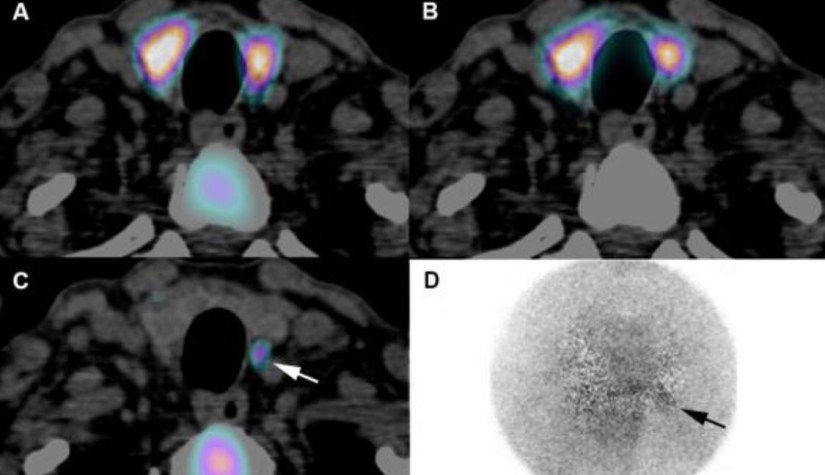

👉The combination of 123I/99mTc-sestamibi subtraction planar pinhole scintigraphy with SPECT/CT and ultrasound improves the specificity of gland localization for minimally invasive parathyroidectomy.